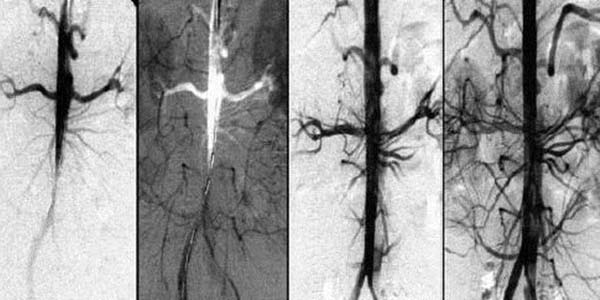

Przez 1,5 miesiąca przyjmowania Cardiotonus

przywracane jest krążenie krwi o 99,71%.

Krążenie krwi zostaje przywrócone systemowo – we

wszystkich naczyniach, tętnicach i naczyniach włosowatych.

Rozpuszcza blaszki miażdżycowe, skrzepy krwi i wapń. Zwiększa światło naczyń krwionośnych do 99,71% normy i przywraca krążenie krwi.